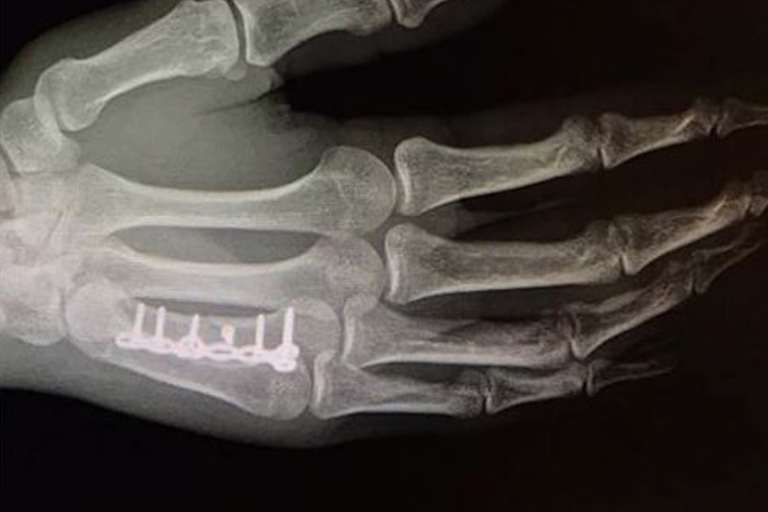

Genau 51 Punkte Rückstand hat Herlings jetzt schon auf Tabellenführer Antonio Cairoli (KTM). Herlings blieb wie Max Nagl (Husqvarna), Romain Febvre (Yamaha), Tim Gajser und einige andere Fahrer in dem berüchtigten Schlammloch hängen und vergrub seine KTM in dem weichen Morast. Der Holländer haderte in Asien zusätzlich mit seiner gebrochenen Mittelhand. Der Bruch ist keine 3 Wochen alt und nur verschraubt. Von einer Verheilung kann keine Rede sein. Im Schlamm ist das Sturzrisiko entsprechend höher und damit die Gefahr, dass bei einem Crash die frisch verschraubte Bruchstelle erneut aufbricht.